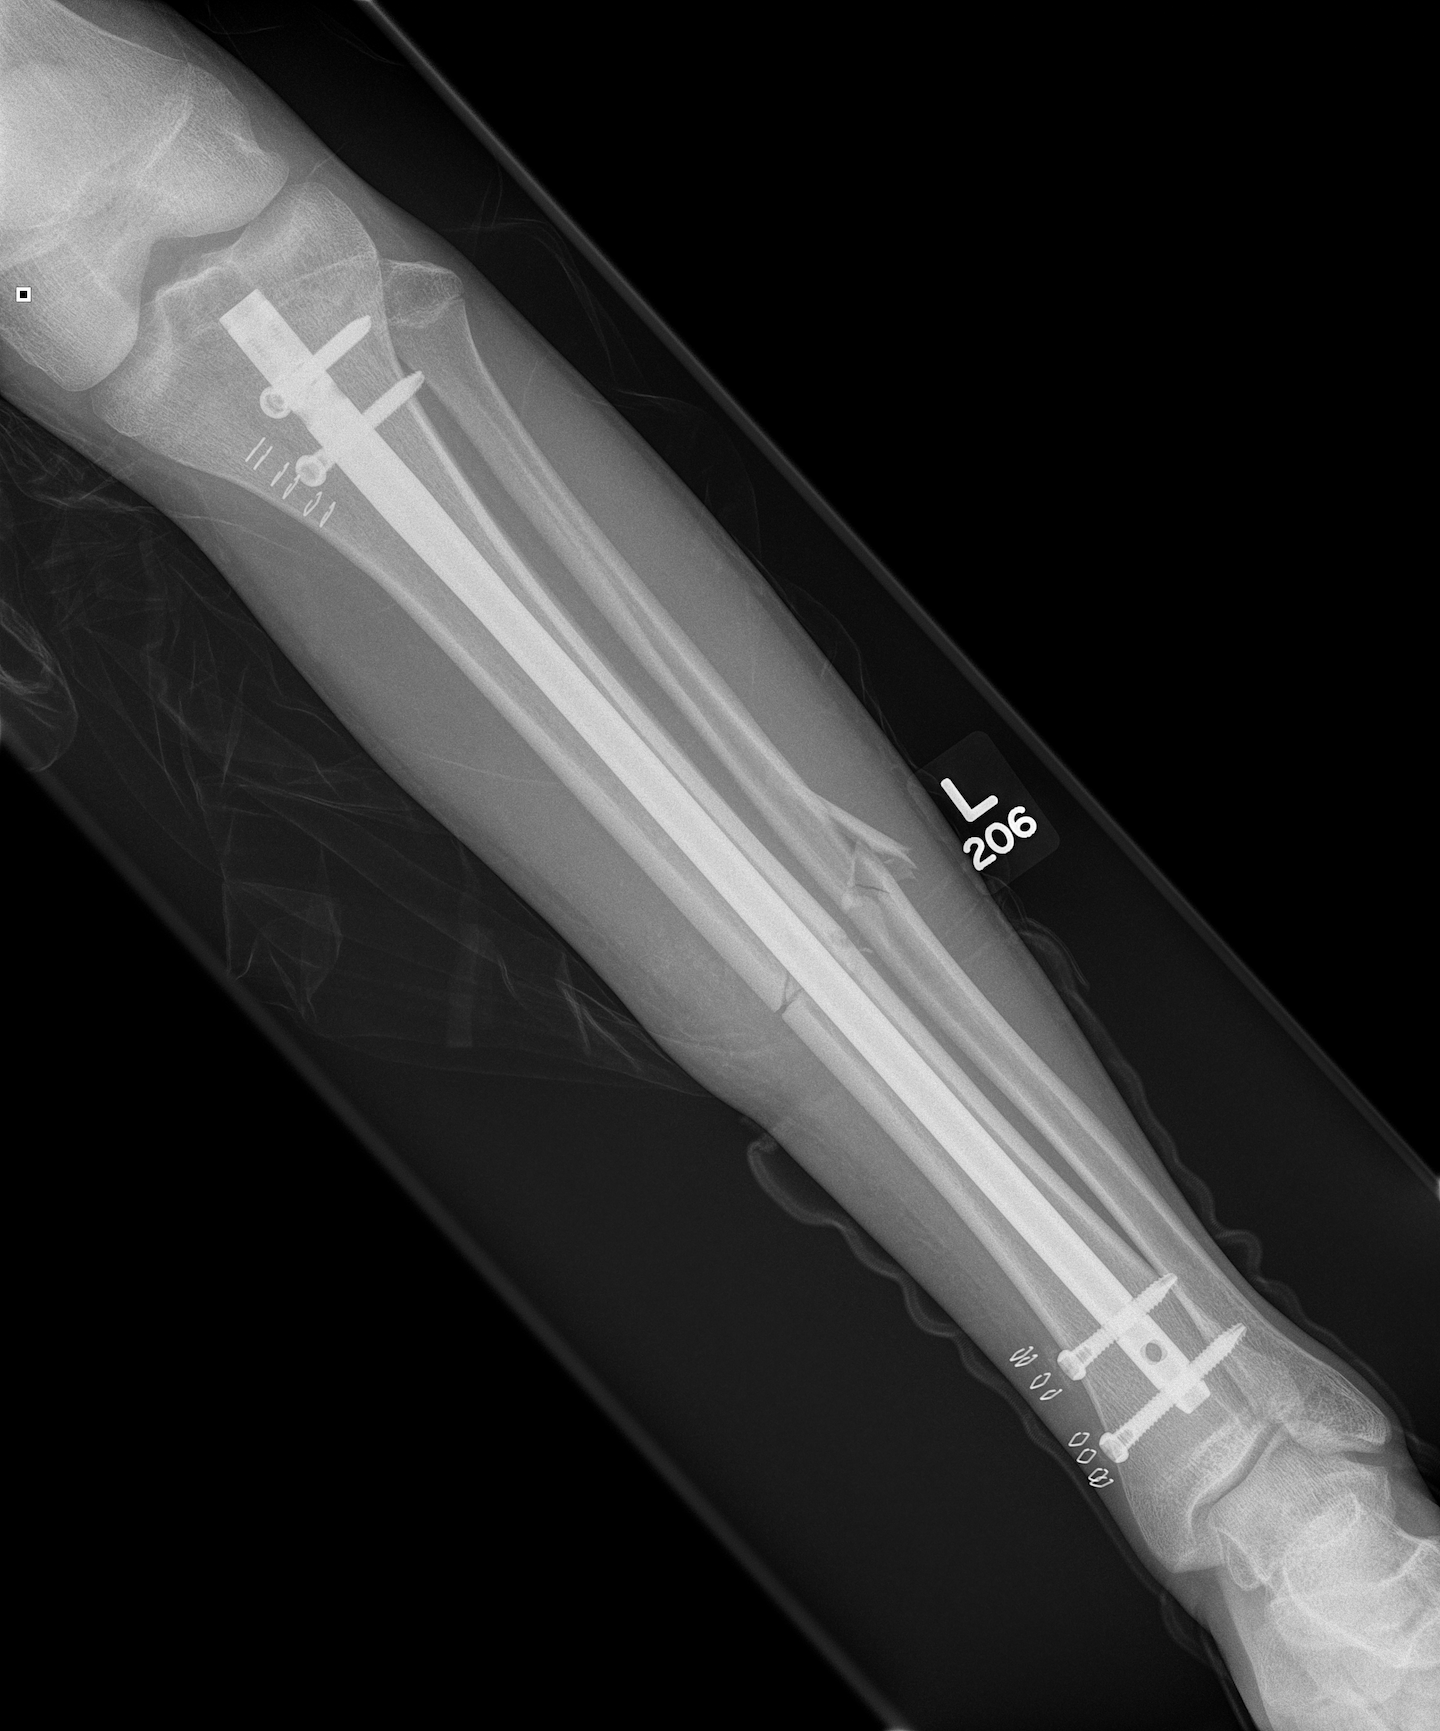

Segmental shaft fractures

Segmental tibia 1Segmental tibia 2

Corey et al J Orthop Trauma 2018

- 95 treated with IMN

- nonunion rate 10%

https://pubmed.ncbi.nlm.nih.gov/29432320/